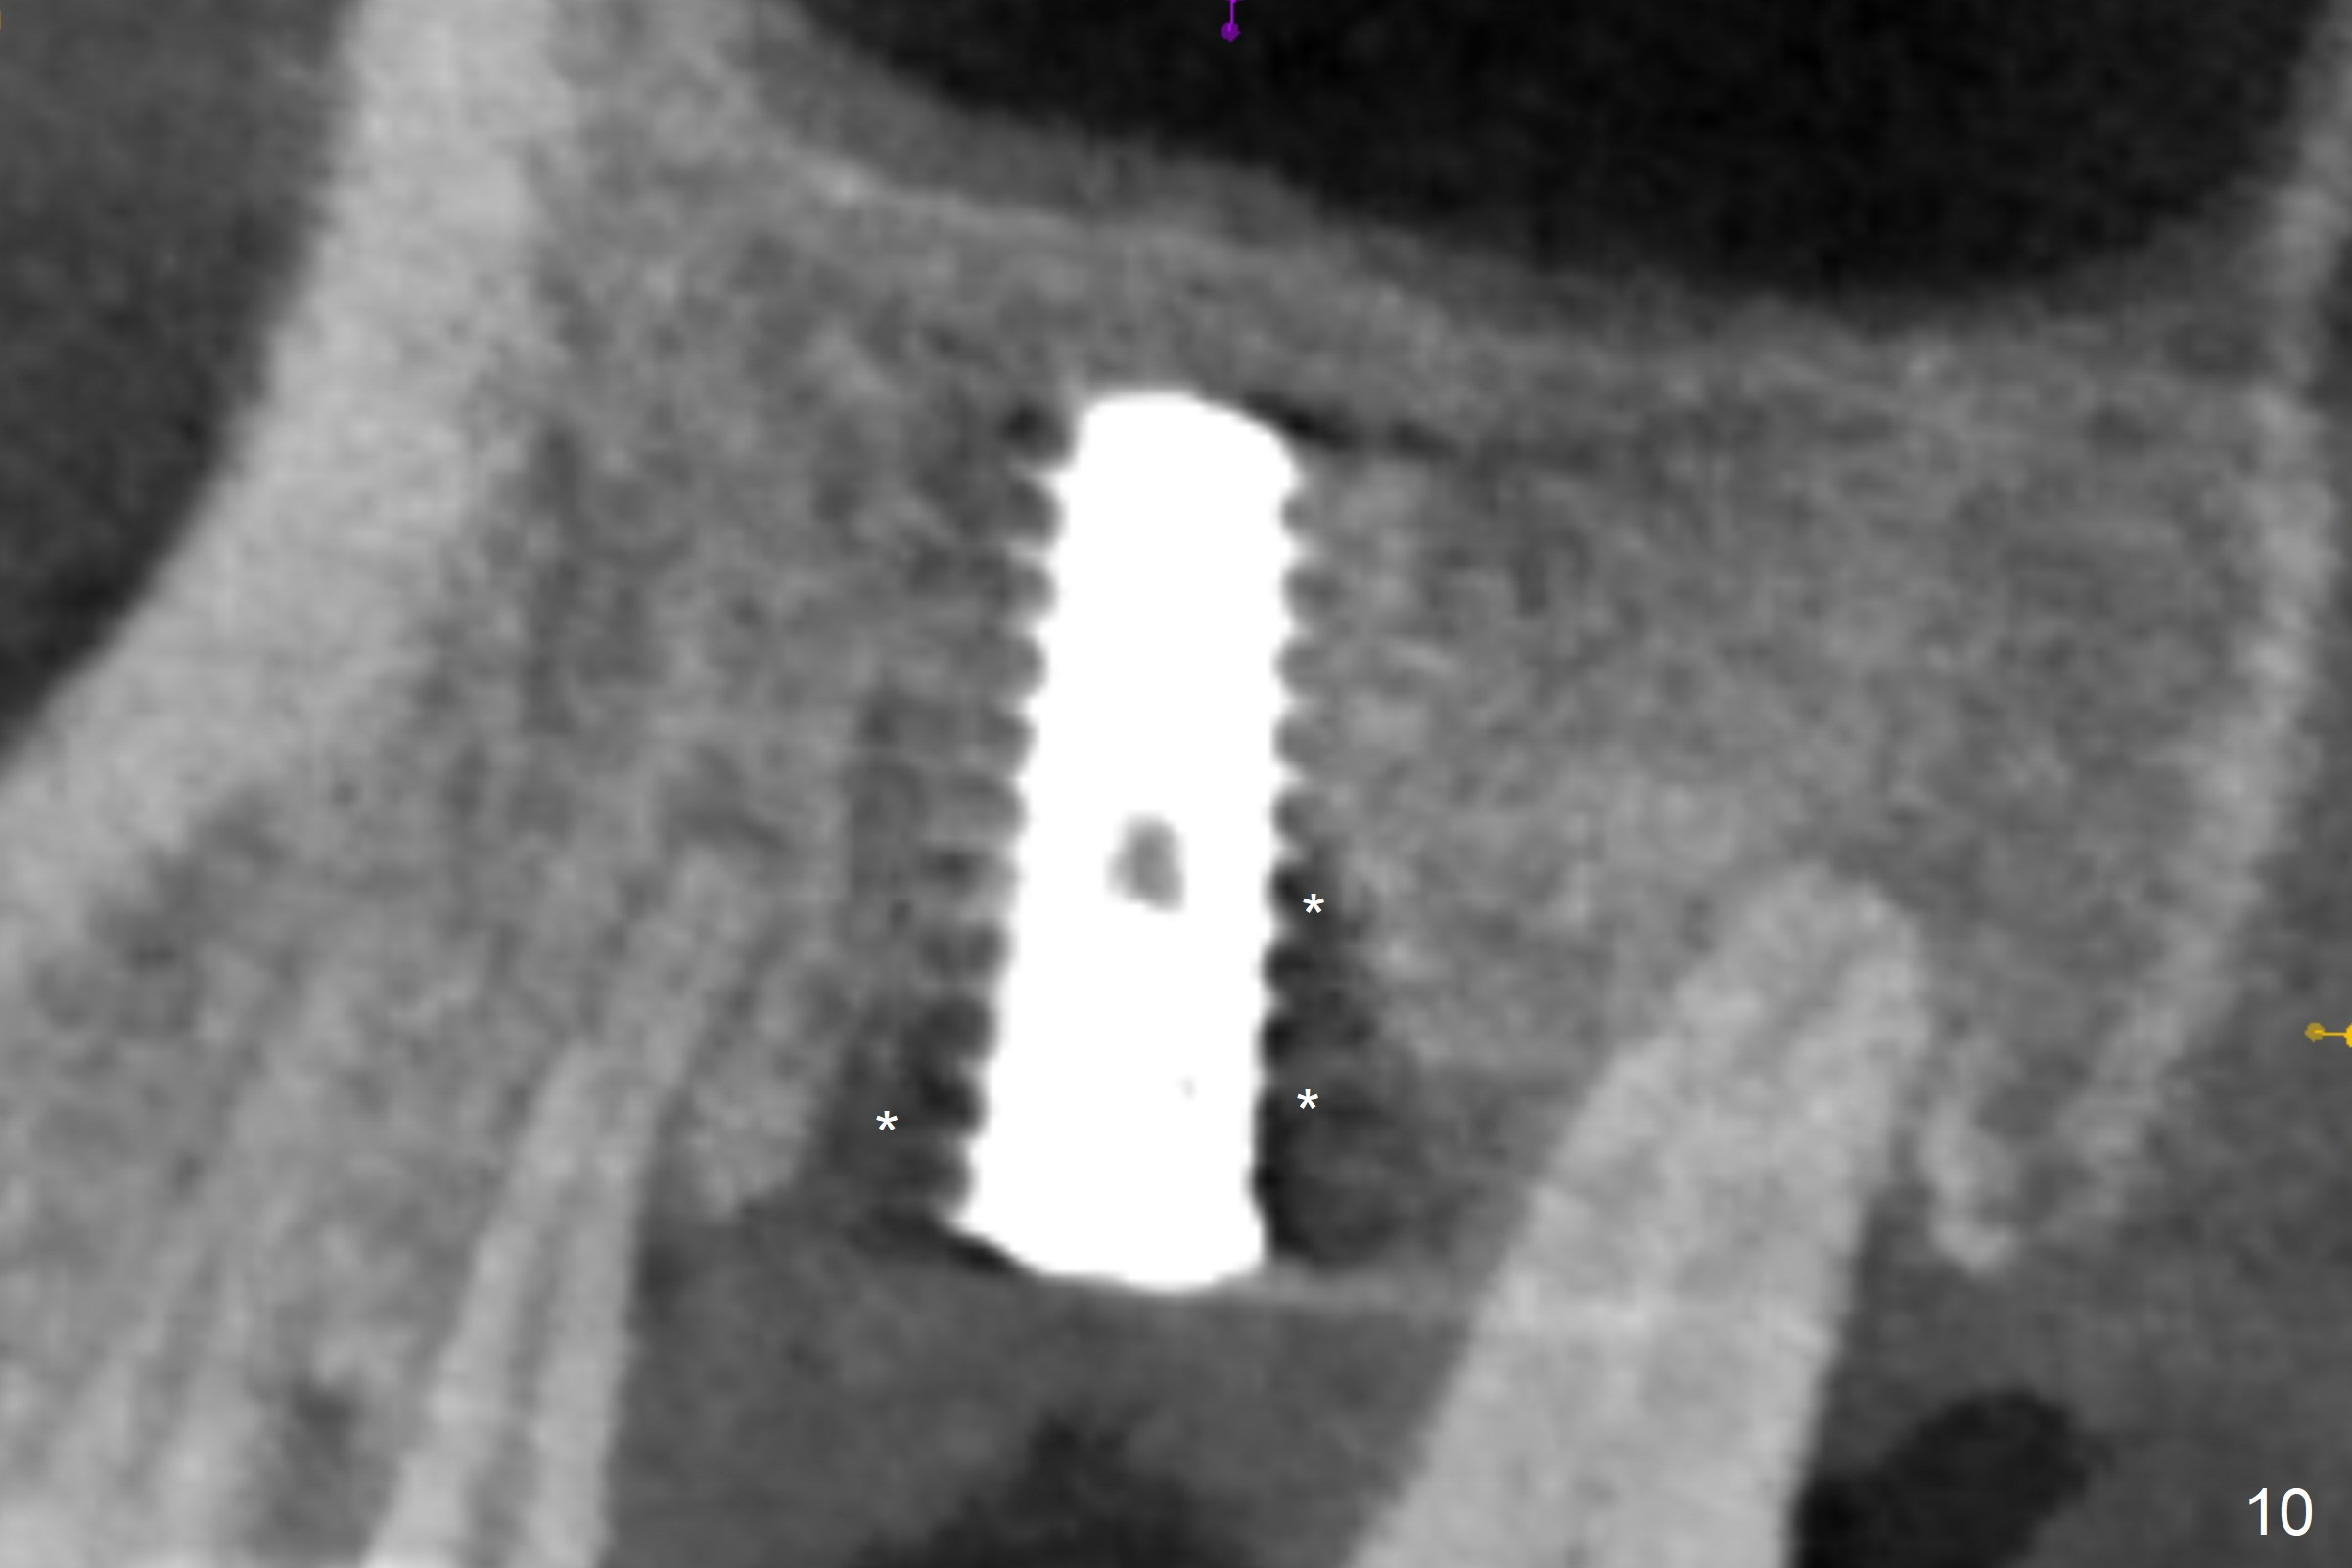

The amount of the bone graft mesial and distal the implant seems to reduce 3 and 4 months postop, respectively (Fig.6,7 arrowheads). When the acrylic is cut off 4 months postop, the bone graft is loose. The gingiva is unhealthy. The abutment and implant are loose. A healing abutment is placed (5x4 mm). The implant is torqued to 35 Ncm 6 months postop with the healing abutment reapplied. The patient will return for follow up nearly 9 months postop. A larger healing abutment will be used if the implant is stable. Two weeks later, use a smaller restorative abutment for easy impression. In fact the implant is unstable with #15 mesial shift due to abnormal occlusion with #17 (Fig.8). Bone density around the implant is low (* in Fig.9 (PA), 10,11 (CT sagittal, coronal sections)). A healing screw is placed for self healing. A 2nd option is to remove the implant (Fig.12), BEB (Fig.13) and place the implant deeper (Fig.14) or larger one (5.5-6.5x13 mm). The 3rd option is to place larger and longer implants (Fig.15 (tapered), 16 (cylindrical)). The implant access has partially closed 14 months postop, but there is a small buccal opening with sanguine exudate. Incision reveals severe bone loss around the implant; the mobile tooth #15 is extracted (Fig.17). After debridement and irrigation with normal saline, Vera Graft (Fig.18 *) and Collagen plug are placed with periodontal dressing.